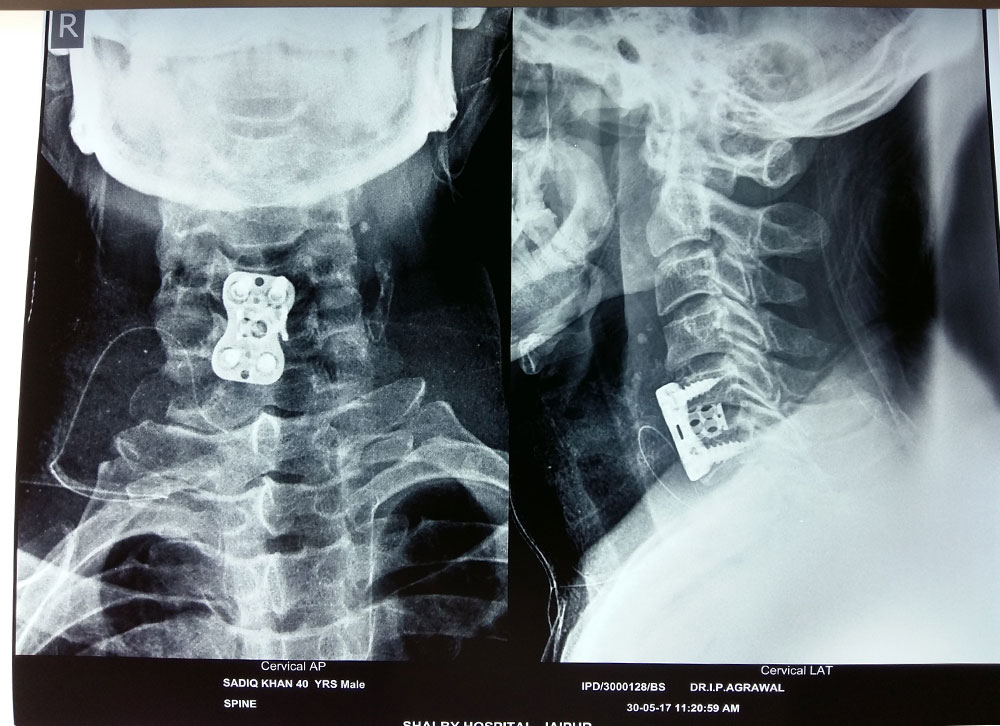

Anterior cervical discectomy and fusion